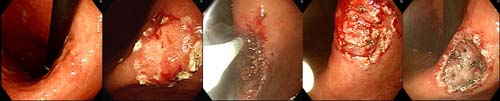

³»½Ã°æÀû Ä¡·á¸¦ ½ÃÇàÇϰí ÀÖ½À´Ï´Ù. ´ÙÀ½

±×¸²Àº Á¶±â À§¾Ï¿¡¼ IT-Knife¸¦ ÀÌ¿ëÇÏ¿©

Á¶±âÀ§¾ÏÀ» ÀýÁ¦ÇÏ´Â Àå¸éÀÔ´Ï´Ù.